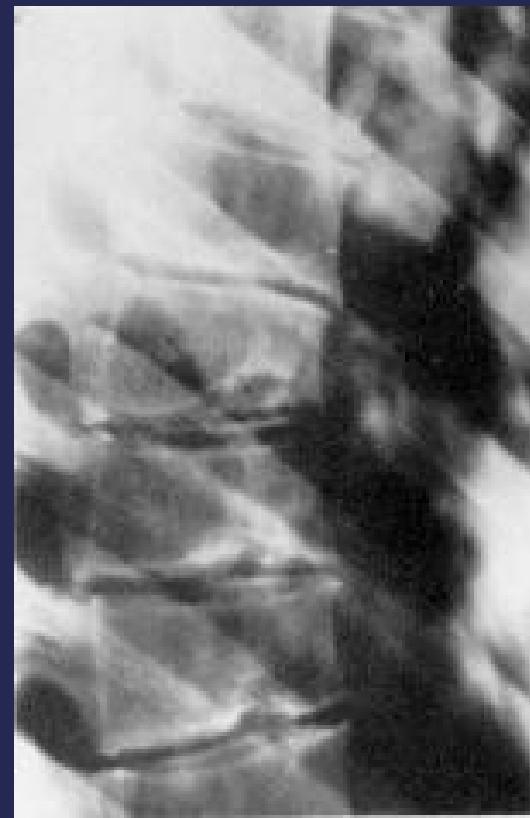

- Irregular ossification of vertebral body epiphysis

- Central herniation of disc material into the body (Schmorl’s Node)

- Wedging of vertebrae

Radiographic Findings:

- Schmorl’s nodes -Central herniation of disc material into the body

Pathology

X-ray Findings

- Schmorl’s nodes (central disc herniation)

- Vertebral wedging